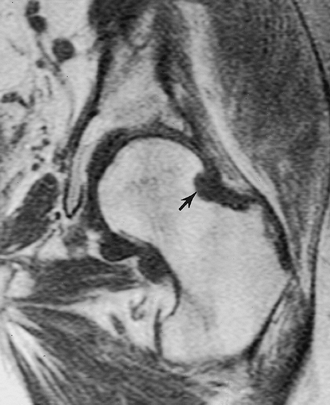

![]() |

FIGURE 4-44 (A) Normal sacroiliac joints. (B) Bilateral sacroiliac ankylosis and spine changes of ankylosing spondylitis.